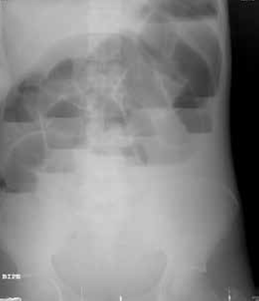

Entre sus exámenes de laboratorio se destacaba una hipopotasemia leve; en el estudio de radiología simple de abdomen, en bipedestación y posición supina, se observó un patrón de ‘pilas de monedas’ (figuras 1, 2, 3).

Figura 2. Radiografía simple de abdomen en supino: distensión de asas de intestino delgado, con patrón de ‘pila de monedas’.